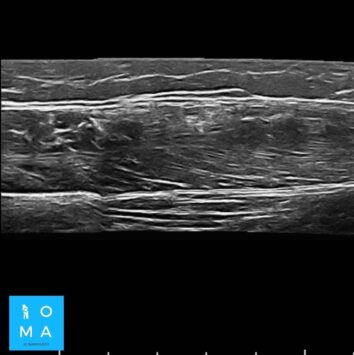

🔹Cambios inflamatorios asociado a edema y banda líquida que rodea a la unión miotendinosa central del sector medio del músculo recto anterior del cuádriceps derecho, de 10 mm de extensión, evocador de desgarro de la unión miotendinosa grado II.